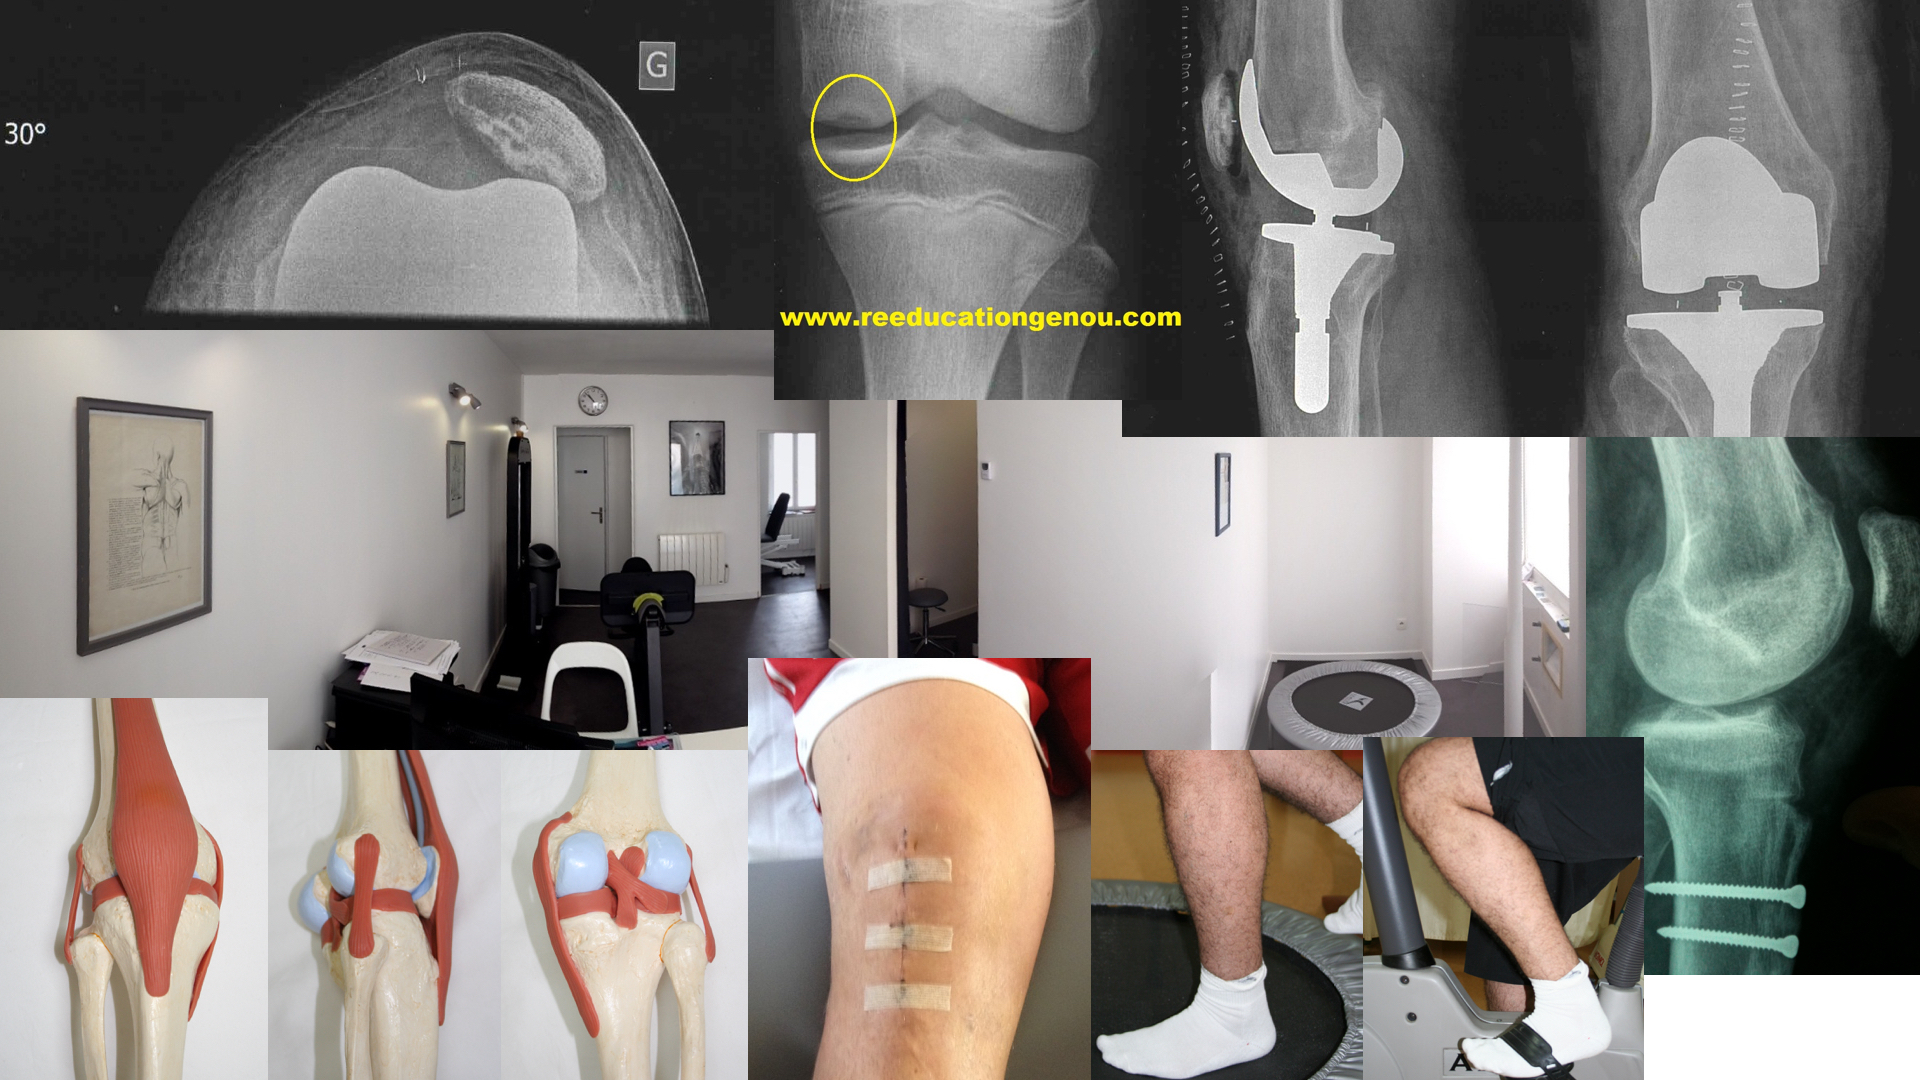

Les lésions ligamentaires du genou

Pour faire simple, les ligaments servent à stabiliser une articulation.

Pour le genou il y a 4 voire 5 ligaments essentiels :

• Les 2 ligaments croisés ils sont dans le genou. on ne peut pas les palper

• le Ligament Croisé Antérieur = LCA (constitué de 2 faisceaux AM antéro médial et PL postéro latéral)

• le Ligament Croisé Postérieur = LCP qui est parfois aussi décrit avec 2 ou 3 faisceaux

• les lésions des ligaments croisés donnent cliniquement des tiroirs lors du test de Lachman

• le LCA rompu donne un tiroir antérieur du tibia (test de Lachman en flexion 30°)

• inversement le LCP rompu donne un tiroir postérieur du tibia (voire un faux tiroir antérieur, et donc un faux Lachman de retour de tiroir postérieur)